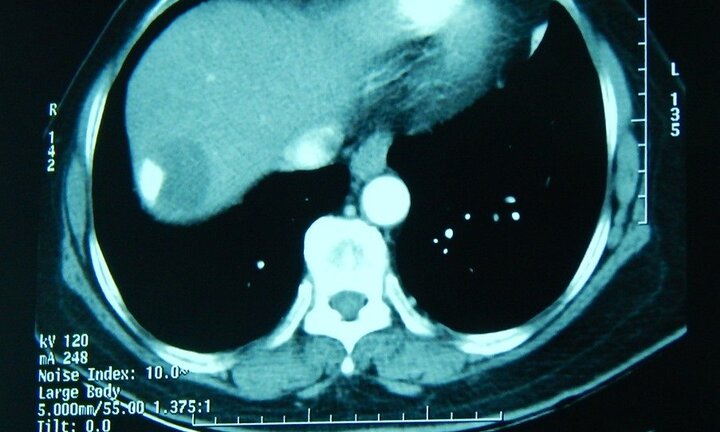

Phá thành công khối u gan kích thước lớn dính liền màng phổi

Bệnh viện nhân dân 115 vừa phẫu thuật thành công khối u gan có kích thước lớn dính liền màng phổi với kích thước 6x7cm cho một bênh nhân 67 tuổi.